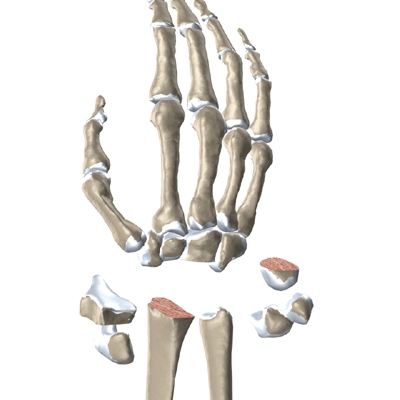

The wrist is made up of eight separate small bones, called the carpal bones. The carpal bones connect the two bones of the forearm, the radius and the ulna, to the bones of the hand. The metacarpal bones are the long bones that lie mostly underneath the palm. The metacarpals are in turn attached to the phalanges (the bones in the fingers and thumb).

Modern artificial wrist joints are made of metal and plastic. The part that fits against the end of the radius bone of the forearm is called the radial component. It is made up of two pieces. A flat metal piece is placed on the front part of the radius. It has a stem that attaches down into the canal of the bone. A plastic cup fits onto the metal piece, forming a socket for the artificial wrist joint.

The part that replaces the small wrist bones is called the distal component. This piece is made completely of metal. It is globe shaped to fit into the plastic socket on the end of the radius. The metal distal component is attached by two metal stems that fit into the hollow bone marrow cavities of the carpal and metacarpal bones of the hand.

The plastic used in artificial joints is tough and slick. It allows the two pieces of the new joint to glide easily against each other as you move your wrist. The ball and socket allow movement of the wrist in all directions.

The surgeon needs to make room for the artificial joint. To do this, most of the first row of:

Carpal Bones are Removed

from the wrist. The end of the radius is also shaped to fit the prosthesis.